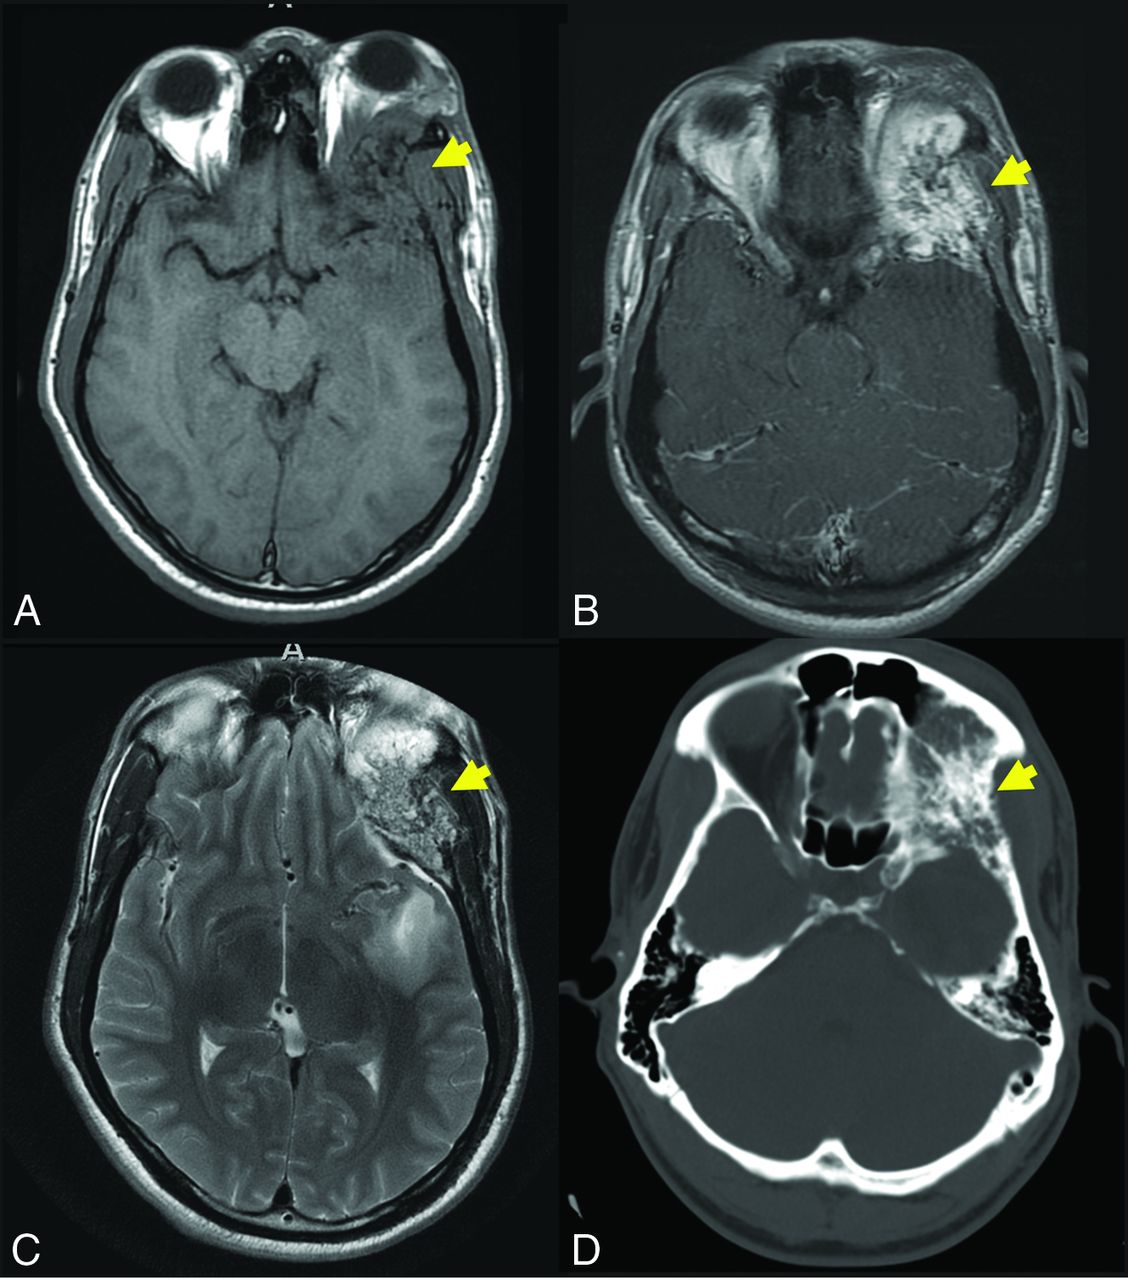

Axial T1-weighted (C) and axial T1-weighted C+ (B) demonstrate an expansile lesion centered within the left greater wing of the sphenoid, with internal T1-hypointense trabeculae and avid enhancement (yellow arrows, A and B). There is mass effect on the left orbit, with resultant proptosis. Axial T2WI (C) demonstrates that the lesion is heterogeneous but predominantly T2 hyperintense (yellow arrow, C). There is vasogenic edema in the subjacent left temporal operculum, presumably based on mass effect, a response to hypervascularity, and venous congestion. Axial CT (D) is confirmatory for the diagnosis of the IOVM, given the presence of thickened internal trabeculae (yellow arrow, D) in a characteristic pattern. The patient was treated with surgical resection. The diagnosis of IOVM was confirmed on pathology, which showed dilated thin-walled blood vessels distending and replacing medullary bone. C+ indicates with contrast. Case courtesy of Phillip Chapman, MD, Professor of Radiology, Duke University School of Medicine.